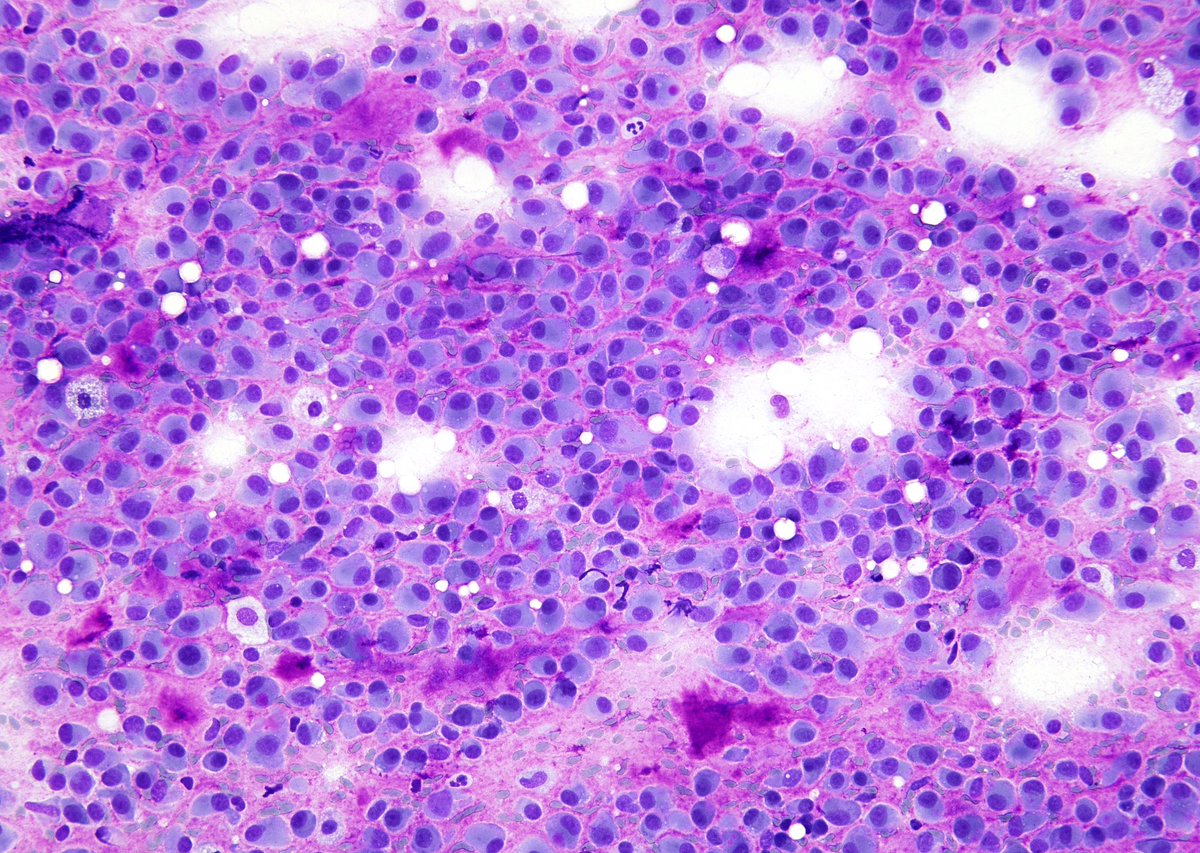

"BOW TIE". Papillary thyroid carcinoma. #FNA Thyroid. #Entpath #endopath #pathology #pathtwitter #PathTweetAward @MSWPathology @MyCytopathology @SamKhader

Head & Neck Pathology #ENTPath. Cytopathology, #FNApath